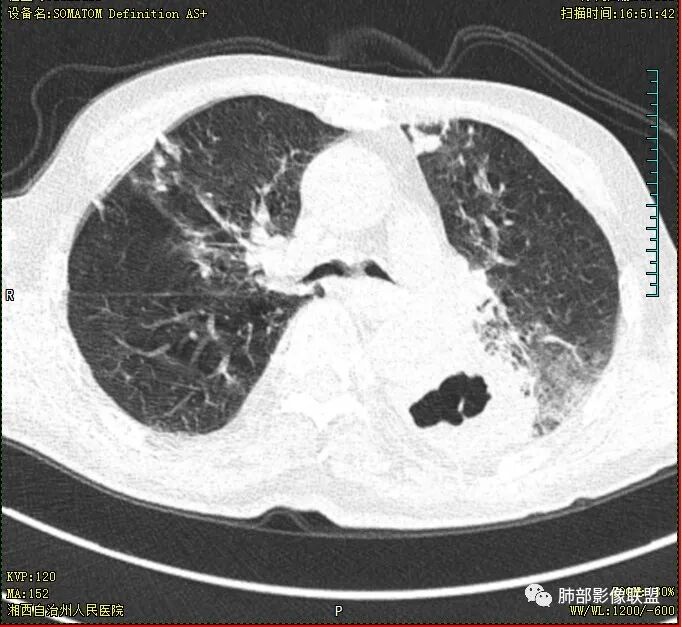

晨读 双肺多发斑片、斑点影,可见树芽征,支气管播散,右肺上叶小空洞,左肺下叶厚壁空洞,内壁较光整,有浅液平,右下叶背段支气管变窄,不均匀强化。结合临床考虑结核并感染,待排除合并肺癌可能。

晨读:老年男性患者,痰中带血伴间断发热2周,体温39.4℃,白细胞、中性粒细胞,CRP增高,Tspot阳性,胸部CT:双肺病变,左肺下叶背段大片实变密度影,边界模糊,内部见空洞形成,空洞内壁总体光滑,有气液平,增强扫描轻度不均匀强化,一月后复查空洞消失,实变影吸收减少,考虑感染性病变,结核伴肺脓肿。

晨读,老年男性,中等病程,咳嗽,痰中带血,发热,主病灶位于左肺下叶空洞,厚壁,偏心,内壁光滑,边界清楚,不均匀强化,内有坏死,考虑结核,内有气液平,周围部分小叶中心结界,好热,白细胞升高,合并感染。结核合并感染,鉴别肺癌合并感染。

老年慢性长期吸烟,痰中带血伴发高热。左下肺大片不均质实变里可见一含气液平厚壁空洞,内壁有坏死物残留,增强可空洞壁明显强化轮廓显示清晰,空洞位于肺门侧,近端支气管壁不规则增厚。两肺散在斑片状影,并见小树芽。18号复查肺窗空洞显示不清,20号用了俯卧位扫描,液体向下流动空洞又显示出来了。左下肺病灶有变小,还是考虑感染性病变,结核合并感染,鉴别鳞癌。

老年患者。左肺下叶厚壁空洞,有液平面。空洞内壁较为光整。病灶的内侧见支气管节段性的变窄扭曲。两肺内,弥漫性的广泛性的播散病灶。考虑感染性病变。肺结核并空洞形成两肺内播散。鉴别诊断-左肺下叶鳞癌。

老年男性,肺气肿,左肺下叶空洞,壁厚薄不均,见液平,下叶支气管阻塞,不均匀强化,伴两肺斑片及树芽影,考虑左肺下叶癌性空洞(鳞癌)并感染及两肺结核

双肺多发结节影,树芽征,小叶中心分布,左肺下叶不规则空洞,洞内壁光滑,见液平,洞壁似与支气管相通,增强扫描明显强化,可见血管造影征。三周左右复查空洞明显缩小。

老年男性,痰中带血,双肺多发点片状阴影,左肺下叶可见空洞影,有液平,不均匀强化,局部低密度区边界不清晰,复查病灶范围缩小,空洞消失,结合病史肿标增高,首选考虑肿瘤合并肺脓肿,鉴别淋巴瘤,结核。

双肺多发点片、索条斑条灶,见多发树丫征,左下肺大片不均质实变,内见一含气液平厚壁空洞,壁厚,内壁有坏死物残留,增强可空洞壁明显强化

,空洞位于肺门侧,近端支气管壁不规则增厚。

首先双肺多灶多形态病灶,考虑结核,聚焦左下肺病灶,空洞,内壁尚光整,有明显液化坏死,增强无明显强化,壁内可见支气管充气征,复查后空洞缩小,首先考虑良性,结核伴脓肿,鉴别鳞癌

胸部CT:双肺多发小斑片、树芽、索条灶,左下肺大片不均质实变,远肺门侧厚壁空洞,气液平,内壁有坏死物残留,增强可空洞壁不均匀强化,近端支气管壁不规则增厚堵塞,实变影内可见与洞壁平行支气管。抗炎3周有缩小。

3.注意到左肺下叶空洞性病灶,腔壁厚度不均,环形强化较为明显,壁间支气管血管影走行,腔内液气平面,这通常见于感染性病灶,如脓肿,经治疗病灶吸收也高度支持病灶主体成分为脓肿。